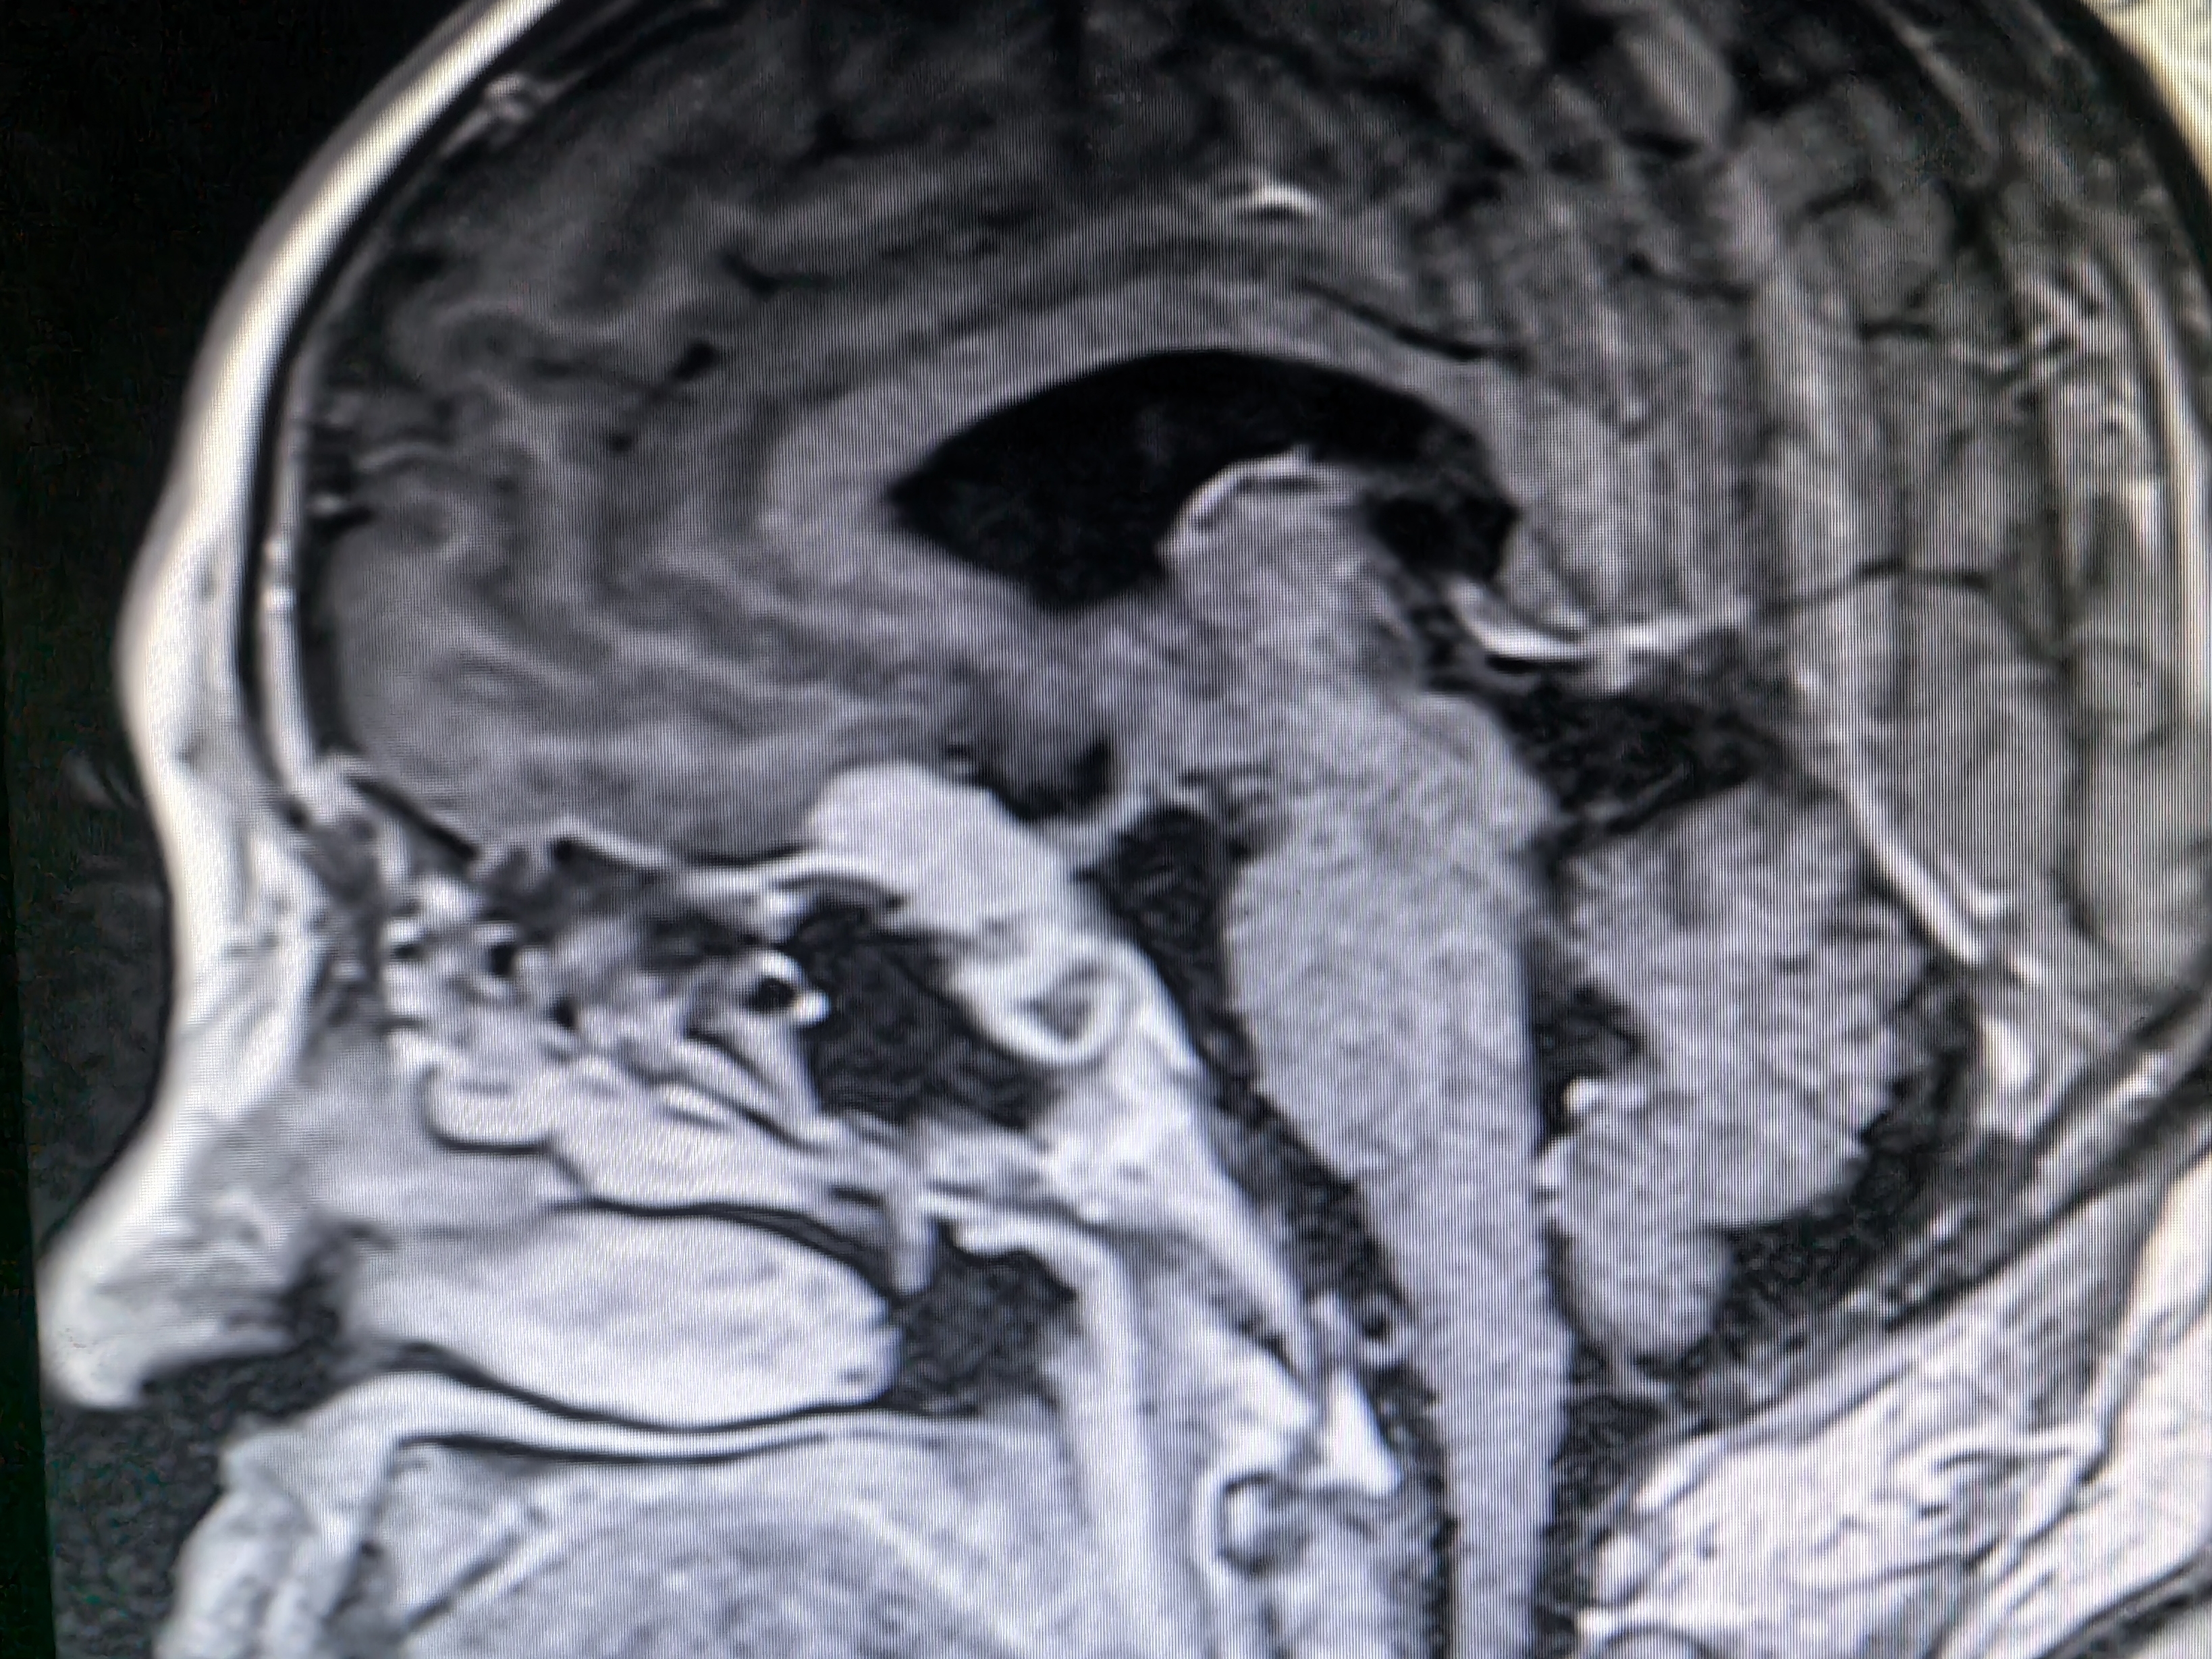

下面展示本病房几例病例:

病例三